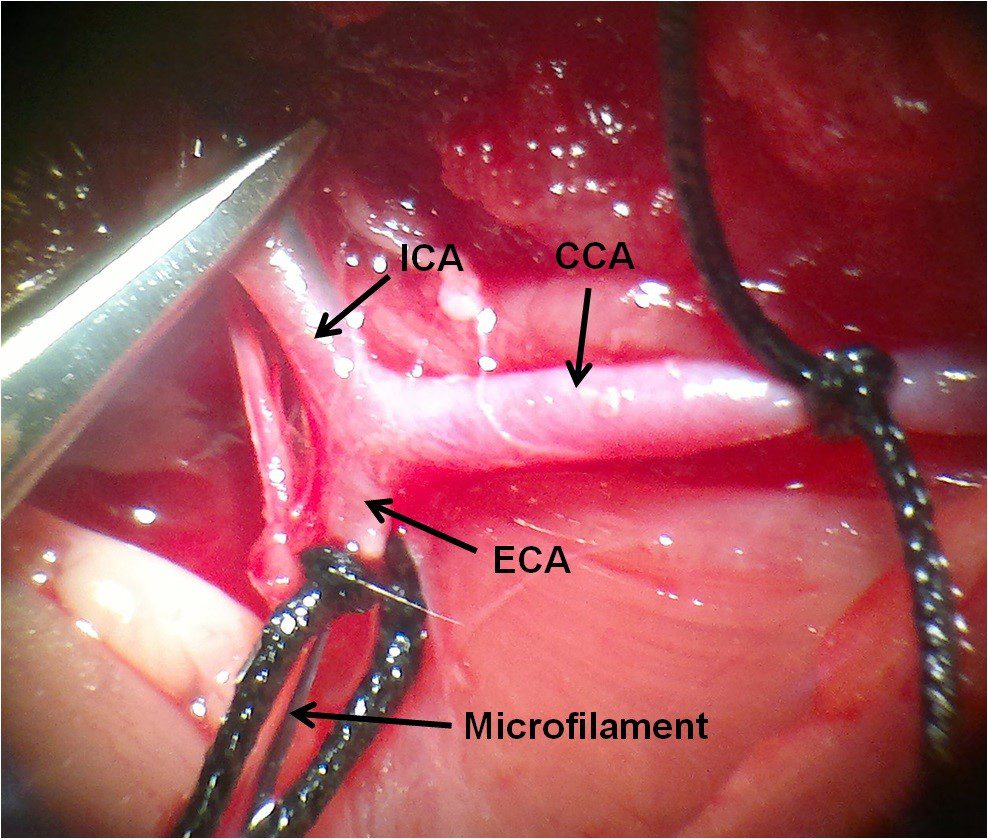

- Surgery and biopsy

- Create and induce a variety of animal models